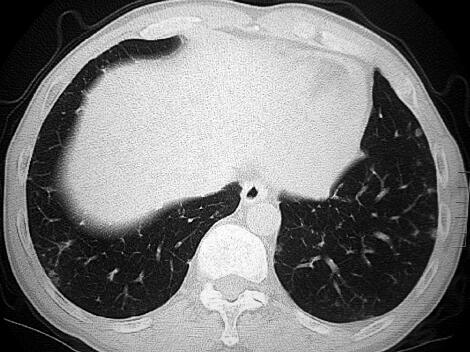

患者为农民,主要从事家务。既往身体健康,无呼吸系统疾病。半年前开始出现少量痰中带血,无明确诱因,其后咯整口鲜血,无胸痛,有轻度活动后气短。于当地诊所检查,胸部CT示双肺多发磨玻璃影,团片影、边缘呈晕轮征(图1)。给予抗感染及止血对症治疗(具体不详),咯血有所减轻。两个月前,患者为明确诊断就诊于我院,进行免疫生化检测时发现P-ANCA(±),诊断为弥漫性肺泡出血,肺血管炎可能性大,止血治疗的同时给予甲泼尼龙治疗,咯血症状消失,气短有所缓解,复查胸部CT:晕轮征及磨玻璃影有所吸收(图2)。继续甲泼尼龙24mg,每日1次,院外口服治疗。患者应用甲泼尼龙1个月后减量至每日20mg,但此后应用不规范,剂量波动于每日16~20mg。患者于入院前半个月再次出现痰中带血,伴胸闷气短,咯血量有增加趋势。

图2

本例患者病初磨玻璃影和晕轮征,结合咯血病史,考虑可能的诊断为血管炎是正确的。同时需要注意晕轮征缺乏特异性,但对缩小鉴别诊断范围有一定的帮助。另外,影像学需要动态评估,第一次就诊,在激素治疗后晕轮征有所吸收,而结节影没有吸收,应引起足够的重视去鉴别恶性疾病,引起晕轮征的常见恶性疾病包括:细支气管肺泡癌,肺鳞癌,肺腺癌,血管肉瘤,骨肉瘤,Kaposi肉瘤等。在诊断不确切时,如果病情允许,应积极进行组织病理学检查。